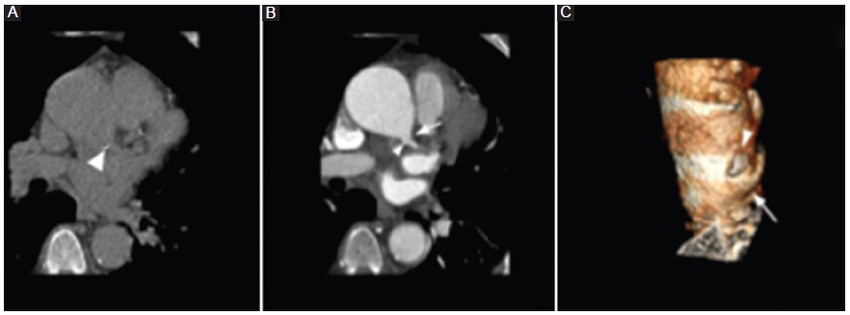

Cirugía de Ross

Esta operación fue ideada para implementarse en niños porque el autoinjerto pulmonar crece con el niño, aunque también puede ser utilizada en pacientes de cualquier edad6.

En el procedimiento de Ross, la válvula aórtica nativa y la raíz aórtica son reemplazadas a 1 cm distal al origen de la arteria coronaria derecha, lo que a su vez permite inspeccionar el estado de la válvula aórtica, la raíz aórtica y el tracto de salida del ventrículo izquierdo durante el acto quirúrgico7. La válvula pulmonar y la porción proximal de la arteria pulmonar del propio paciente se fijan al tracto de salida del ventrículo izquierdo y al anillo aórtico con múltiples suturas de poliéster. A esta arteria aorta tratada se le reimplantan las arterias coronarias, las cuales serán reubicadas en función de la válvula, pudiendo ser esta última subcoronaria, subcoronaria con preservación del seno no coronario, cilíndrica o raíz completa. Finalmente, se restablece el flujo de la arteria pulmonar a través de un injerto sintético o bioprotésico (Figs. 5 y 6) (6,7.

Al igual que otros procedimientos, la cirugía de Ross puede tener complicaciones, entre las que se mencionan el aumento de la regurgitación aórtica y la dilatación progresiva del autoinjerto pulmonar como principales limitaciones6,7.